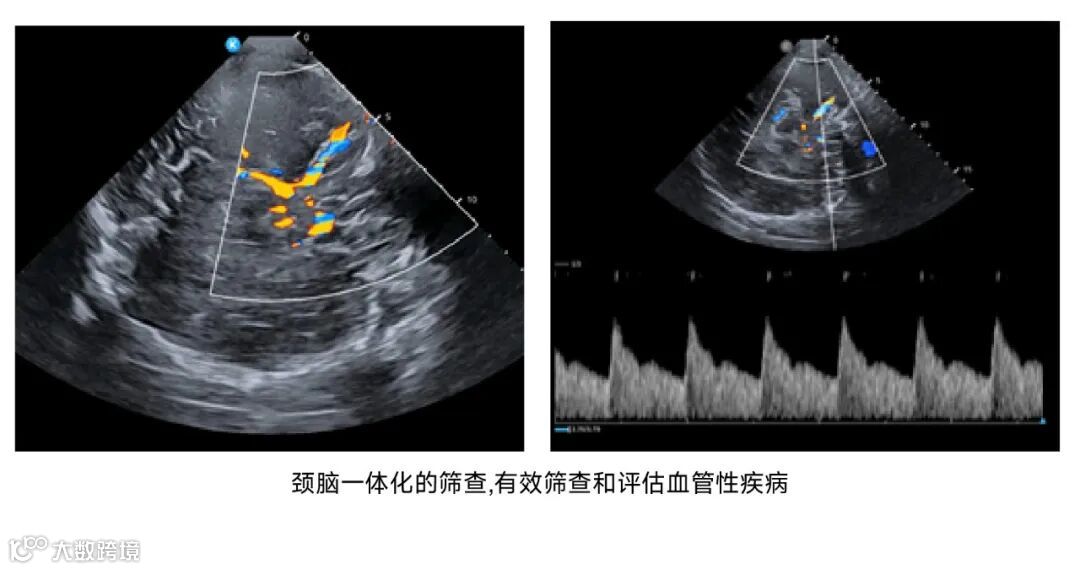

鲲为科技基于kOS带来的超分辨成像技术和超穿探头,

进一步拓展了颅脑超声的应用场景,

在神经内科、神经外科、神经重症监护监测、急诊重症监护、儿科及神经调控等领域带来革命性的创新诊断方案。